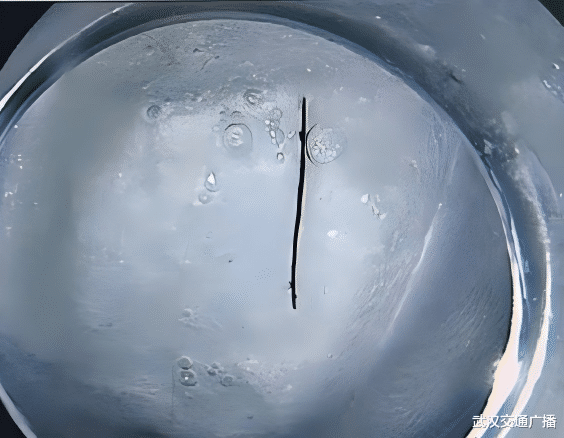

胃镜影像图

竟然,检查发现彭女士胃窦区存在一处约2厘米的黏膜高出,集合后续腹部增强CT影像学检查,进一步证据高出里面躲藏着长条状异物。濒临检查成果,彭女士相配诧异,反复示意我方从未误食鱼刺、骨头等锐利异物。王珣主任说明,“胃镜是消化疾病会诊的‘金圭表’,亦然排查胃部隐退病变最直不雅、最有用的妙技,尤其关于永远不解原因的消化谈症状,时时能发现X光或CT难以捕捉的细小异物。”

为幸免钢针永远淹留,激发黏膜溃疡、出血,致使穿孔等更严重的病变。消化内科团队马上制定内镜下微创异物取出有贪图。大夫在高清胃镜领导下,精果真开胃黏膜,快速取出一枚长约2cm,时势规整的生锈钢针,绝对铲除困扰了患者半年的健康隐患。术后彭女士胃部不适症状赫然缓解,食欲自如规复。